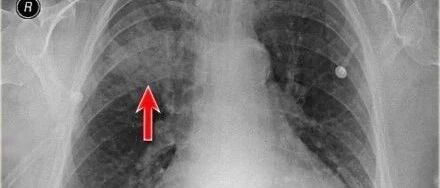

胸疾病胸片表现之肺实变

来源:医脉通呼吸频道